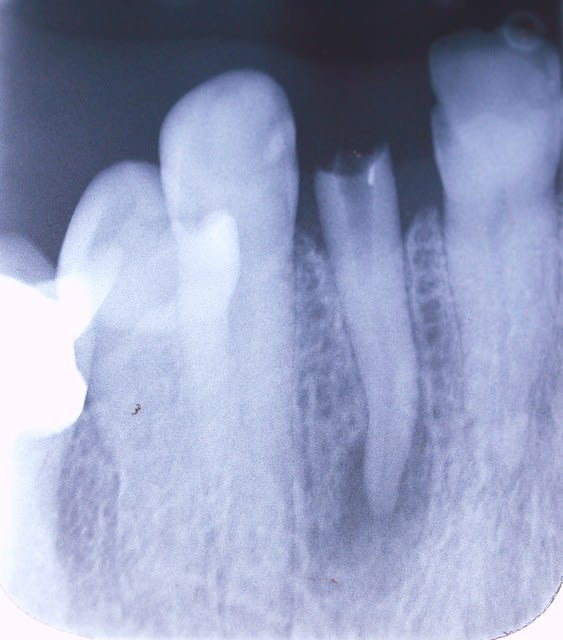

donc je commence normal:

depose ccm (12 bien sur )puis tenon .

bon elle est calcifiée mais pas grave suis un craint degun .

je prends la turbine .tiens c est profond ! change fraise pour une longue encore trop court .touati pareil.

la tete bute sur les 2 autres . finalement quand tu est trop court tu as l air con .

et puis on y voit rien , calcifiée pas question de prendre un foret .

je me suis dit : si je peux pas aller au fond je vais amener le fond a moi.

donc l enlever puis ne pas la remettre a fond au cas un irm a l apex

remerde elle est collée .collée et tordue .

fraise de chir + syndesmotome mecanique monté sur giromatique .

je te fais un alveolo-massacre, que meme dans la CCAM il imaginent pas .plus de crete vest .un ouaille complet.

un aller simple pour la 22